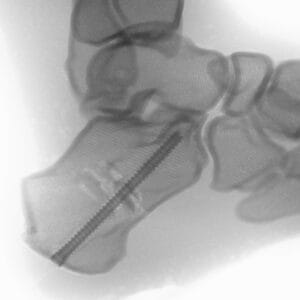

| Pathology | Pes Cavus |

| Procedure | Cole Osteotomy, Dwyer, Lateralizing Calcaneal Osteotomy, Metatarsal Dorsiflexion Osteotomy |

| Area | Midfoot |

Pes Cavus – Bone Model